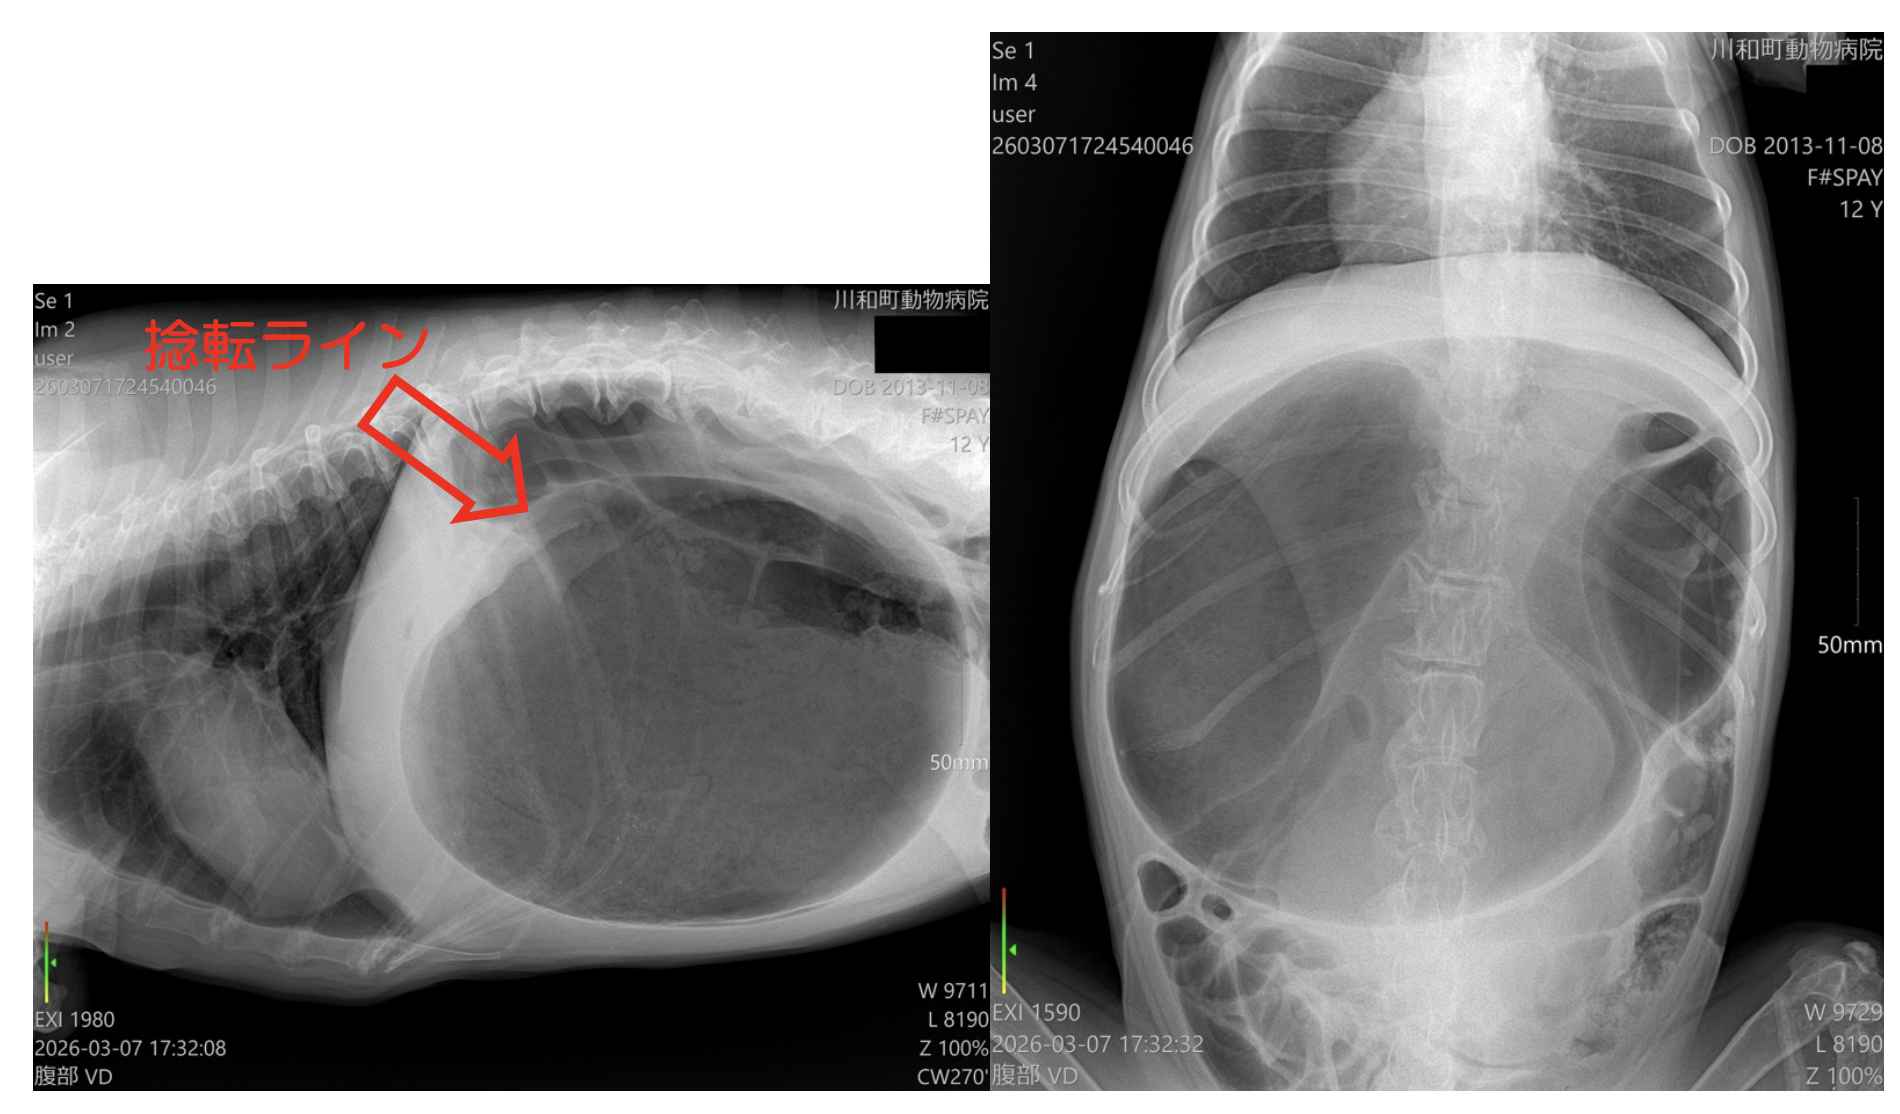

レントゲン 重度胃拡張

右下側面像にて捻転ラインが確認された